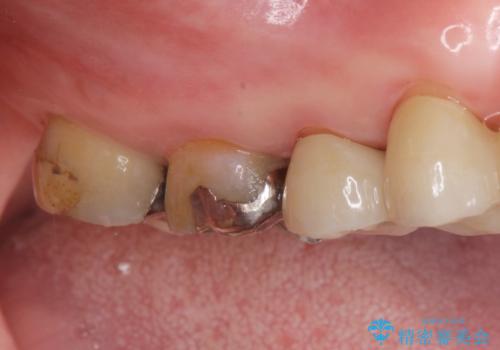

拡大鏡下で虫歯を取り切った後、フルジルコニアクラウンにて治療しました。

適合の良い被せ物が入りました。

メタルの詰め物や被せ物は歯質との間に隙間ができやすく虫歯の原因の細菌が侵入し、虫歯の再発に繋がります。

セラミックの詰め物や被せ物は歯質との間に隙間が出来にくいため虫歯の再発のリスクが低くなります。